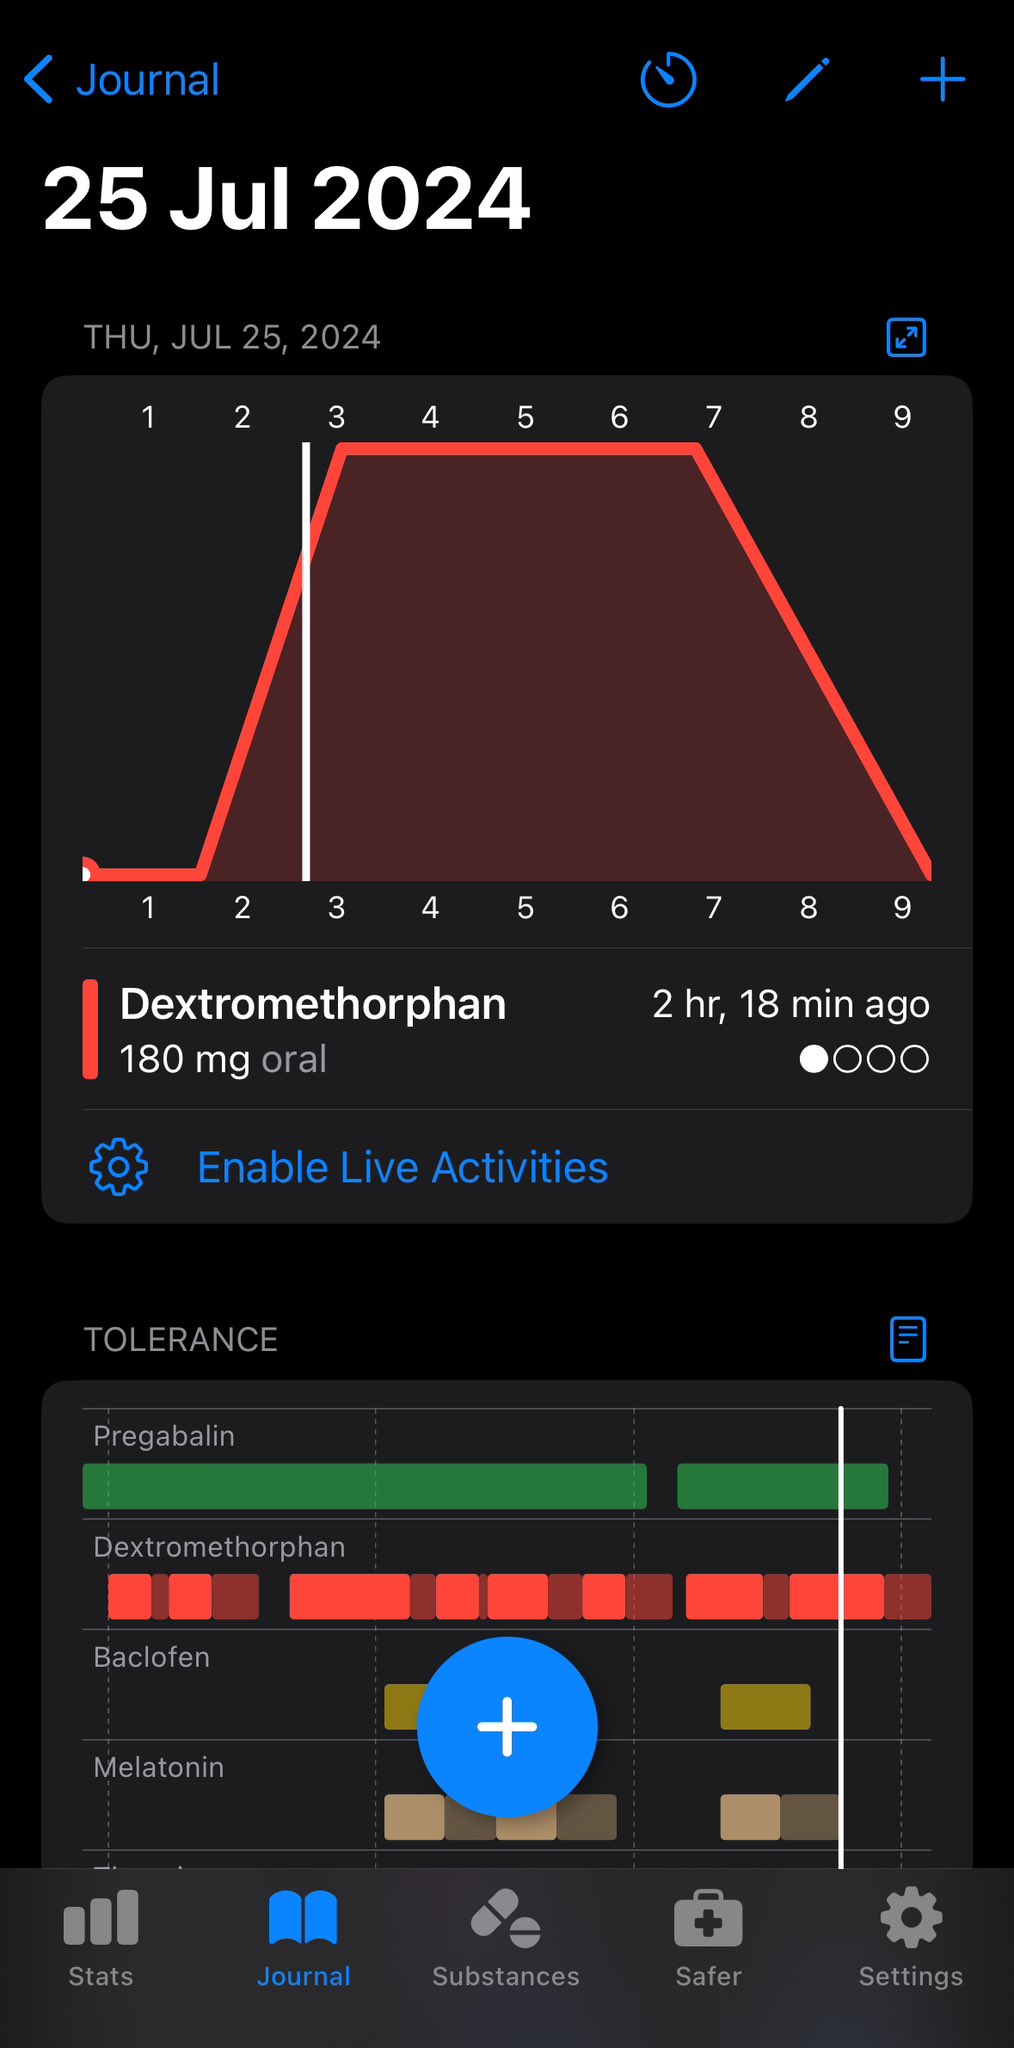

炽烈已极 @AnIncandescence@whitenightX3 journal